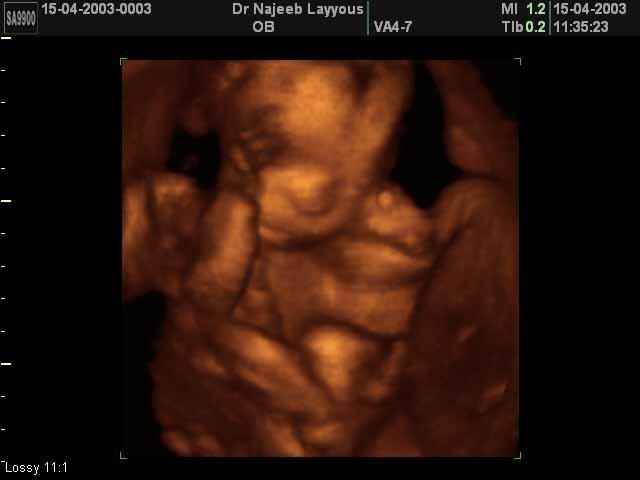

- Fetal Behavior Ultrasound Photos

3D Second Trimester Ultrasound Scan Photos-second part of pregnancy | Dr N Layyous